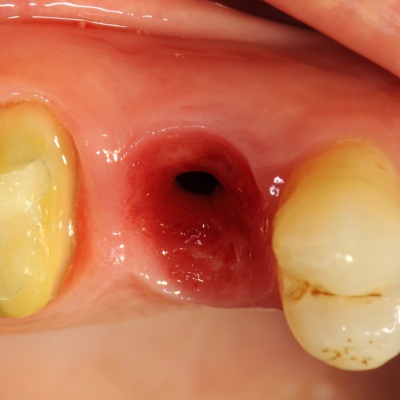

Thématique de cette journée de formation : La théorie de l'extraction/implantation mise en charge/esthétique immédiate, l'application de cette théorie dans des cas d'édentements uniques.